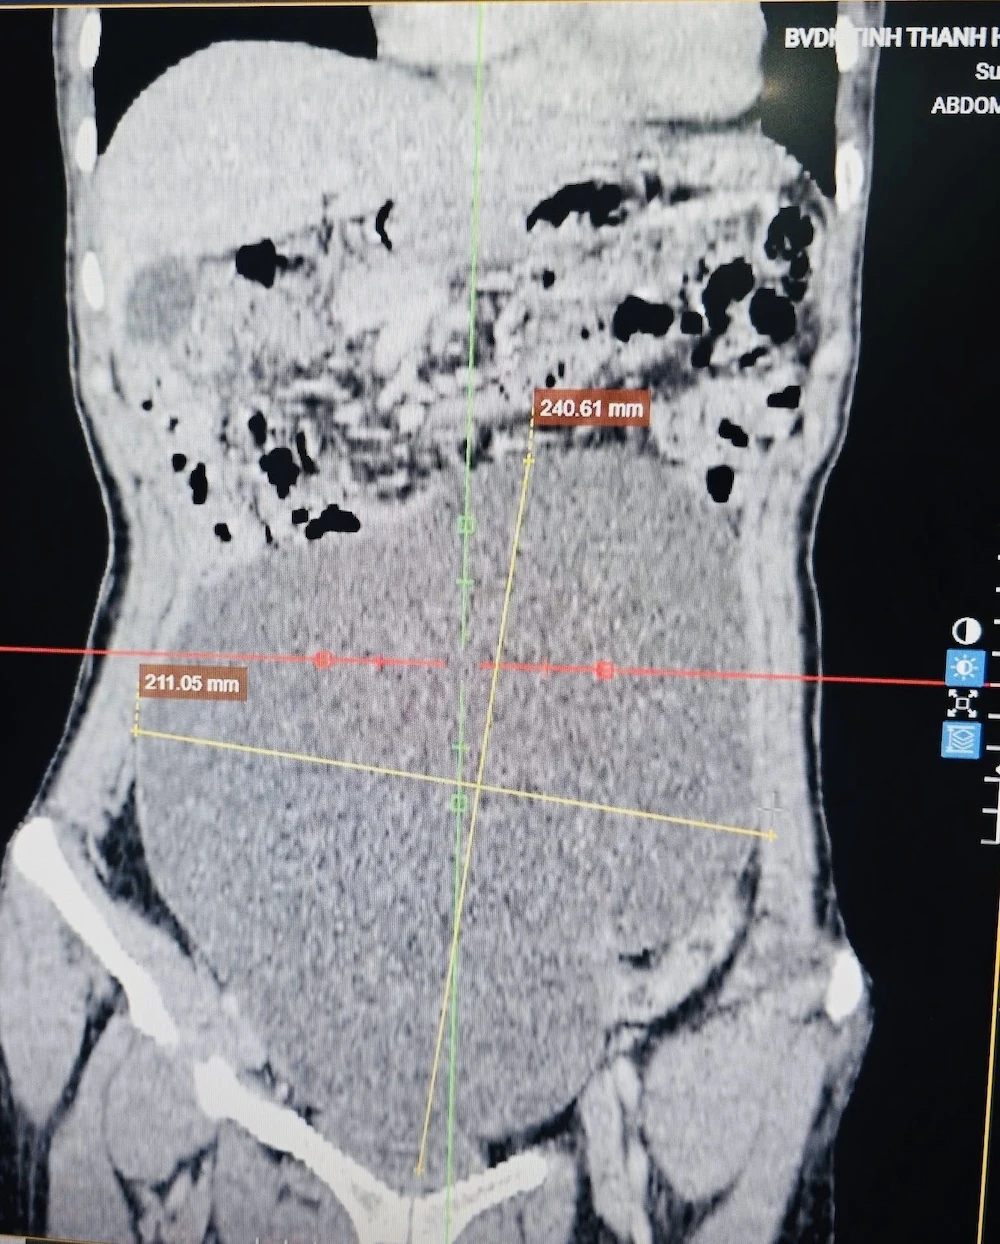

Hình ảnh trên phim chụp CLVT ổ bụng cho thấy khối u chiếm gần toàn bộ ổ bụng.

Bệnh nhân đã được các bác sĩ thăm khám lâm sàng và thực hiện các xét nghiệm cận lâm sàng cần thiết. Kết quả chụp cắt lớp vi tính (CLVT) ổ bụng cho thấy một khối u kích thước rất lớn, chiếm gần toàn bộ ổ bụng, kéo dài từ hạ vị đến thượng vị, xuất phát từ buồng trứng, theo dõi u buồng trứng ác tính.

Ê-kíp phẫu thuật đã bóc tách thành công khối u xuất phát từ buồng trứng trái, kích thước khoảng 25cm, nặng gần 3kg, sau đó gửi mẫu bệnh phẩm làm xét nghiệm mô bệnh học.